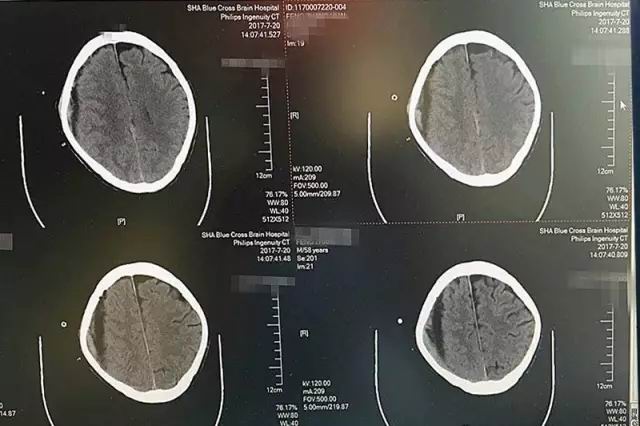

第一天,術(shù)中引流出暗紅色血液120毫升左右,腦CT影像顯示,血腫大部分被吸收。

第二天,又引流出90毫升暗紅色血液,術(shù)后CT顯示血腫基本清除干凈。

第三天,血腫順利被清除,就像工兵搬走了地雷,警報(bào)解除。

紅圈處為高密度引流管,進(jìn)入顱內(nèi)約1.2厘米,后部為放射狀偽影

就這樣,歷經(jīng)三天,72小時(shí),李振并主任成功地為老馮解除了腦出血的威脅,平穩(wěn)又嫻熟地將他大腦右半球的陳舊性出血基本清除干凈。術(shù)后僅三天,我們的老馮就能下地走路了!

患者術(shù)后CT影像顯示:血腫基本被吸收